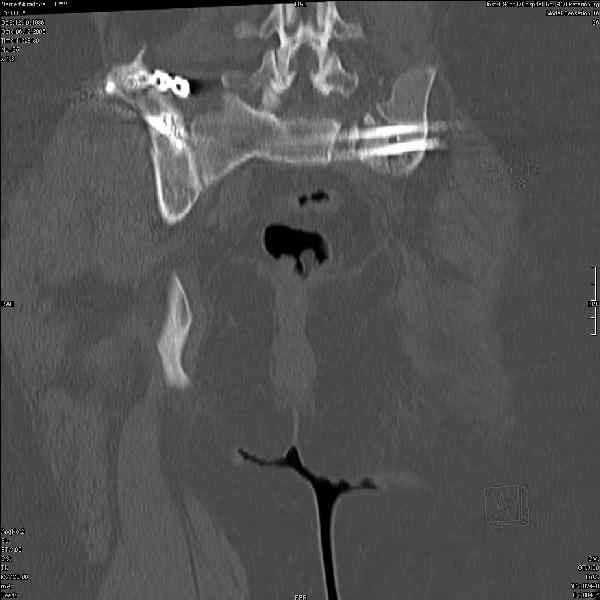

Могу сказать одно: миграция винтов и нестабильность синтеза левого подвздошно-крестцовогоо сочленения очевидна.

Вот цитата из статьи с odoс.ru:"Идеально было бы иметь винты диаметром 7 - 8 мм с довольно широкой резьбой в 50 - 80 мм. Также необходимы более длинные винты и, в общем, наиболее часто используемые размеры - между 90 и 150 мм." Думается, в этой статье вы найдете ответы на все ваши вопросы.

Забыл добавить, что ИХМО показан реостеосинтез более длинными винтами, с более широкой резьбой, с фиксацией за правое подвдошно-крестцовое сочленение.